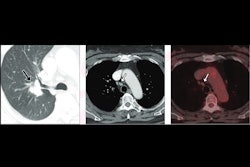

Examples of degrees of fibrosis quantified and radiologically scored. CT pulmonary angiograms (top row) were radiologically scored as having mild (left), moderate (middle), and severe (right) disease; the corresponding output and fibrosis percentage as quantified by the artificial intelligence (AI) model are shown in the bottom row. Images courtesy of the RSNA.